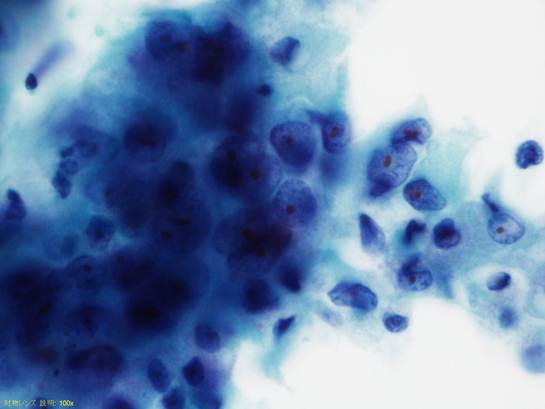

他の視野では重積性があり辺縁にほつれのある細胞集塊や平面的に配列する上皮集塊が認められる。

この集塊の細胞の核は大小不同があり、不整形で核クロマチンが濃染し核小体が目立つ。

細胞質は広く好酸性顆粒をもつものもある。

癌細胞であり多形腺腫由来癌が考えられる。